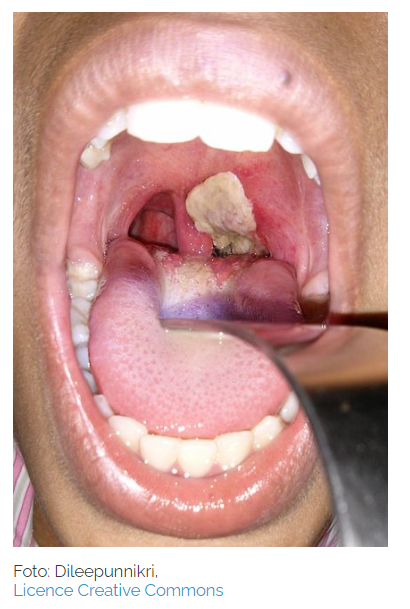

Diphtherie ist eine bakterielle Infektionskrankheit, die sowohl die oberen Atemwege als auch die Haut betreffen kann. Anfängliche Symptome sind Halsschmerzen, Husten und Anschwellen der Lymphknoten. Darüber hinaus bilden sich in Nase, Rachen und in der Luftröhre fest haftende Belege, welche zu Atemnot führen können. Eine Erstickungsgefahr ist bei einem schlimmen Verlauf der Erkrankung nicht auszuschließen. Außerdem ist ein süßlich-fauliger Mundgeruch, der durch ein weißlich-gelblichen Belag auf den Mandeln ausgelöst wird, typisch für eine Diphtherie-Erkrankung. Die Bakterien sondern außerdem Gift ab, welche weitere Organe beschädigen können, wodurch beispielsweise Pneumonien (Lungenentzündungen) oder eine Karditis (Herzentzündung) entstehen können.

Symptome: Häufige Symptome sind Halsschmerzen, Fieber, Schluckbeschwerden und Schwächegefühl. Später können noch Heiserkeit, Anschwellen der Rachen- und Kehlkopfschleimhaut hinzukommen. Bei schwerem Verlauf kann es auch zu Atmen Problemen bis hin zur Erstickung kommen. Gelangt das Toxin des Bakteriums in den Blutstrom, kann es Schäden an Herz, Lunge sowie Nieren verursachen.